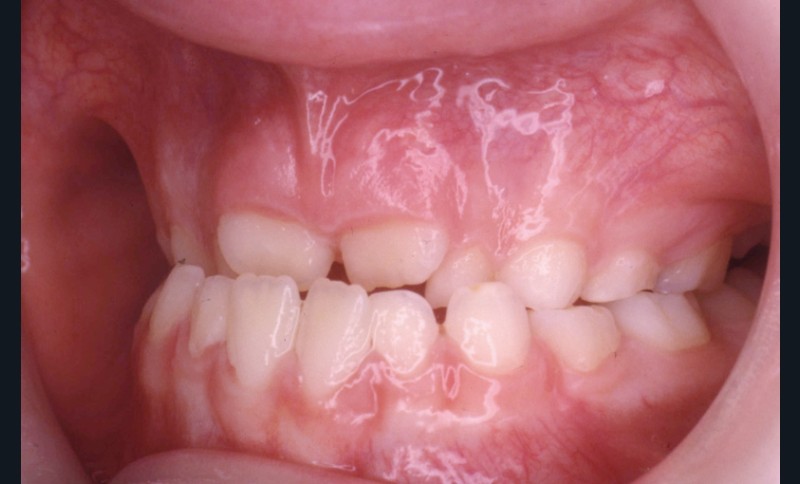

L’examen de la denture (fig. 3 à 5) montre :

• dans le sens antéro-postérieur, des relations molaires et canines de type classe III d’Angle et une inversion des rapports incisifs,

• dans le sens transversal, une endomaxillie bilatérale prédominante dans la région canine.